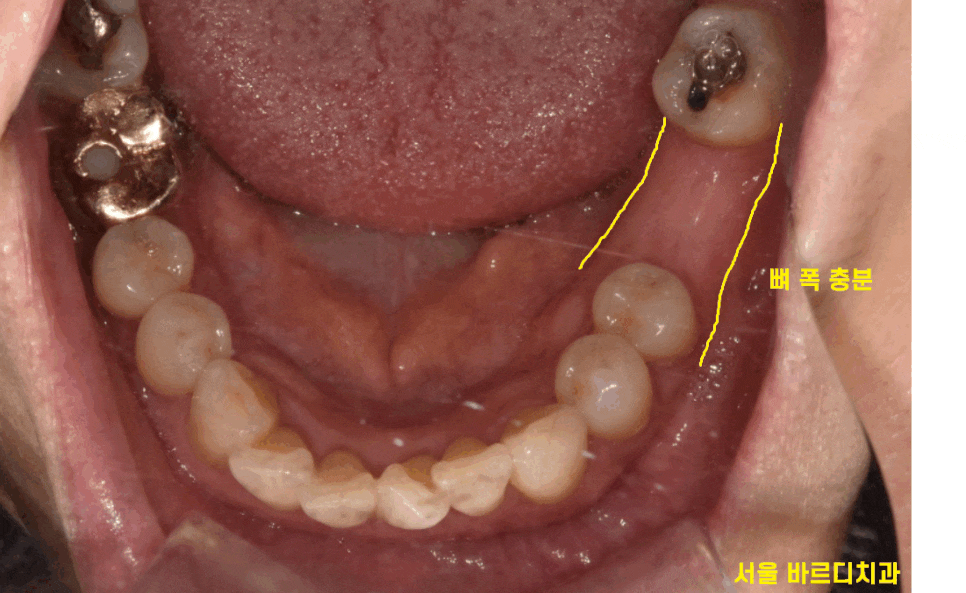

제일 정확한 것은 직접 보아야겠죠?

이어진 입 안 검사

환자분 입안을 보았을 때

뼈 폭도 충분해 보였습니다.

아래 어금니 임플란트 1개라

더 기다리지 않고

그냥 심어도 될 수준이었습니다.